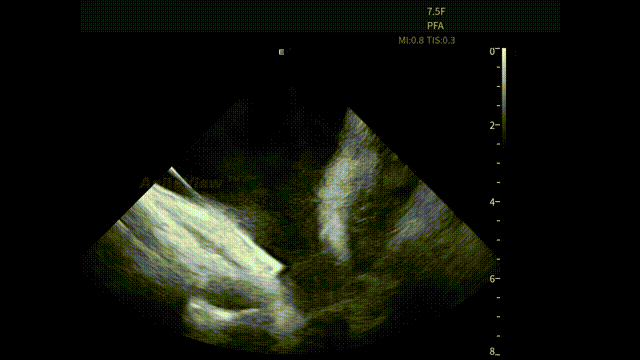

术中,基于AgileView™ ICE 7.5F的产品优势,蒋晨阳主任团队将ICE导管打A弯跨三尖瓣进右室,松弯卡室上嵴,顺转后打到左房长轴切面,以便更好地进行导管封堵/贴靠与位置的判断,在AgileView™ ICE实时影像的指导下,PulseSelect™ 脉冲消融导管安全进入左心房,先后完成双侧肺静脉隔离及MTI、roofline、后壁BOX、SVC隔离, ICE下可见导管贴靠良好,整个消融过程顺利,消融时间约50分钟。术后患者恢复良好。

房间隔穿刺-导丝进入上腔

房间隔穿刺

导丝进LSPV

左房长轴一嵴部贴靠